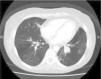

A 38-year-old female ex-smoker was diagnosed with acute leukemia and treated with chemotherapy, radiotherapy and subsequently received allogeneic bone marrow transplantation from an unrelated HLA-identical donor. After the procedure, she developed cutaneous and pulmonary graft-versus-host disease and repeated respiratory infections. She was admitted for hemoptysis of approximately 50cm,3 with no clinical symptoms of infection. She had very mild leukocytosis, mild hypoxemia and increased density in the left lower lobe. Chest CT scan revealed occupation of the segmental bronchi in the left lung base (Fig. 1). Bronchoscopy showed a highly vascularized endobronchial mass with whitish plaques. The biopsies did not reveal malignancy. After endobronchial laser resection, the biopsy was reported to be adenocarcinoma with mucinous areas, of pulmonary origin. Immunohistochemistry was positive for cytokeratin 7 (CK7) and carcinoembryonic antigen. Left lower lobectomy with mediastinal lymphadenectomy was performed by video-assisted thoracoscopy. A brown 3-cm endobronchial polypoid lesion with preserved bronchial epithelium lining was identified. There was involvement of the bronchial wall, but no extension beyond it. There was no infiltration into the lung parenchyma or vascular bundle. The growth pattern was glandular, with abundant mucoid material. No mitosis, nuclear pleomorphism, or necrosis were observed. Neoplastic cellularity was CK7-positive, while thyroid transcription factor-1 and chromogranin were negative, with isolated positivity for p63. The final diagnosis was low-grade endobronchial mucoepidermoid carcinoma, with a free surgical margin and hilar nodes with no neoplastic involvement. The patient continues to be followed up with regular visits, and no tumor recurrence has been detected to date.